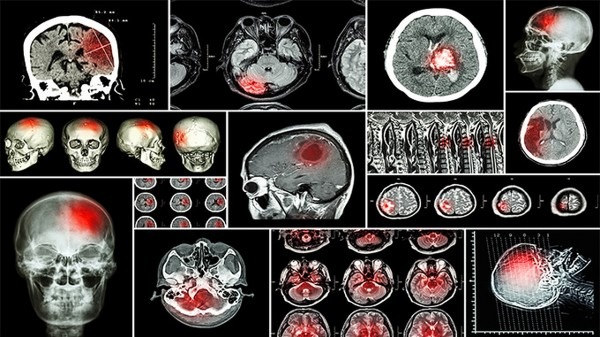

Turcot综合征是一种罕见的遗传性疾病,主要表现为结直肠癌或中枢神经系统肿瘤。这种疾病通常与遗传性多发性息肉病(FAP)或遗传性非息肉病性结直肠癌(HNPCC)相关联。患者常常在年轻时就会出现结直肠癌或脑部肿瘤的症状,给患者及其家庭带来巨大的身体和心理压力。

Turcot综合征的诊断需要通过基因检测和家族史调查来确认。一旦确诊,患者需要接受个体化的治疗方案,通常包括手术切除肿瘤、化疗和放疗等治疗手段。同时,患者和家人也需要接受心理辅导和遗传咨询,以更好地应对这种罕见疾病带来的挑战。